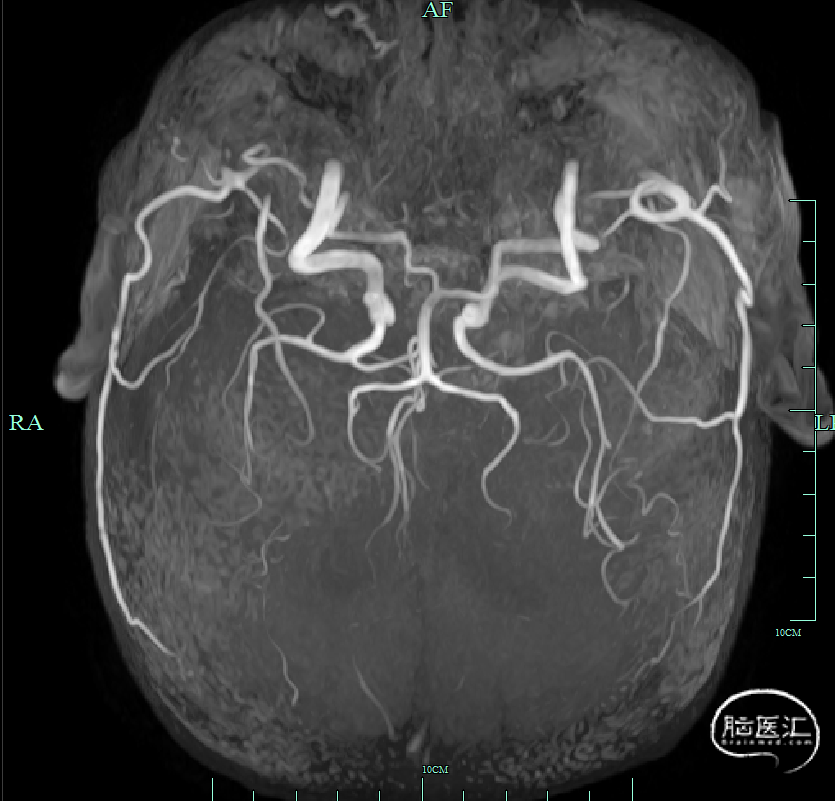

➤术后影像

术后第一天,头颅DWI可见尾状核及基底节区新发脑梗死;MRA可见右侧颈内动脉、右侧大脑中动脉、双侧大脑前动脉无再次闭塞。